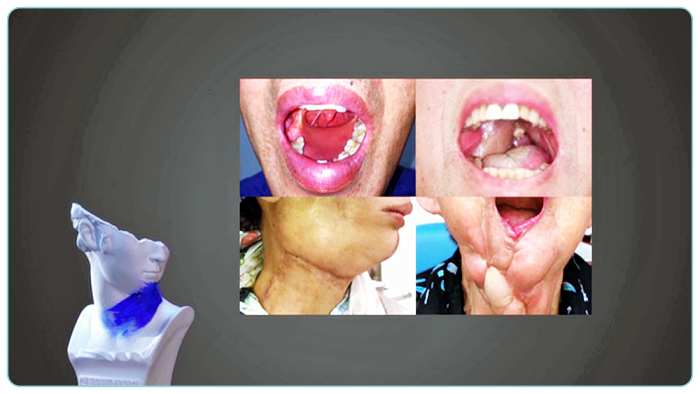

두경부암 (후두암, 구강암, 편도암를 비롯한 구인두암, 비인두암)은 초기일 경우 뚜렷한 증상이 없다. 증상이 생긴다 해도, 입안에 생기는 궤양이나 부종, 목소리 변화나 목에 잡히는 멍울이 대표적이다. 하지만 이런 증상은 일시적으로 나타나는 것일 수도 있기 때문에 많은 사람들이 병원 진료를 미루곤 한다. 그래서 더 빨리 발견하기 어려운 암... 그것이 바로 ‘두경부암’이다.

30대의 최 씨...입에 돋은 혓바늘 때문에 통증이 심했다. 혓바늘은 4주 이상 사라지지 않았다. 하지만 별 대수롭지 않게 여겼고, 동네 병원에서 진통제만 처방 받으며 일상생활을 했다. 그런데... 그것은 뜻밖에 암이었다. 구강암의 일종인 혀암. 심지어 암은 다른 장기로 전이된 상태였다.

입에 생기는 궤양이나, 음식을 삼킬 때 느껴지는 이물감, 그리고 목소리의 변화, 목의 통증 등... 구강암을 비롯한 두경부암 (후두암, 구강암, 편도암를 비롯한 구인두암, 비인두암)의 증상은 무척 다양하다. 하지만 그 중에 공통적인 증상이 하나 있다. 그것은 바로 목에 생기는 혹이다.

두경부암 (후두암, 구강암, 편도암를 비롯한 구인두암, 비인두암)의 경우 주로 목에 있는 림프절로 전이되기 때문에, 병이 진행되면 목에 멍울이 잡히기 시작하는 것이다. 하지만 이 혹은 통증이 없다. 그래서 방치하기 쉽다. 너무나 사소해 무심코 지나치기 쉬운 두경부암 (후두암, 구강암, 편도암를 비롯한 구인두암, 비인두암)의 증상...과연 어떤 점에 주목해야 할까?